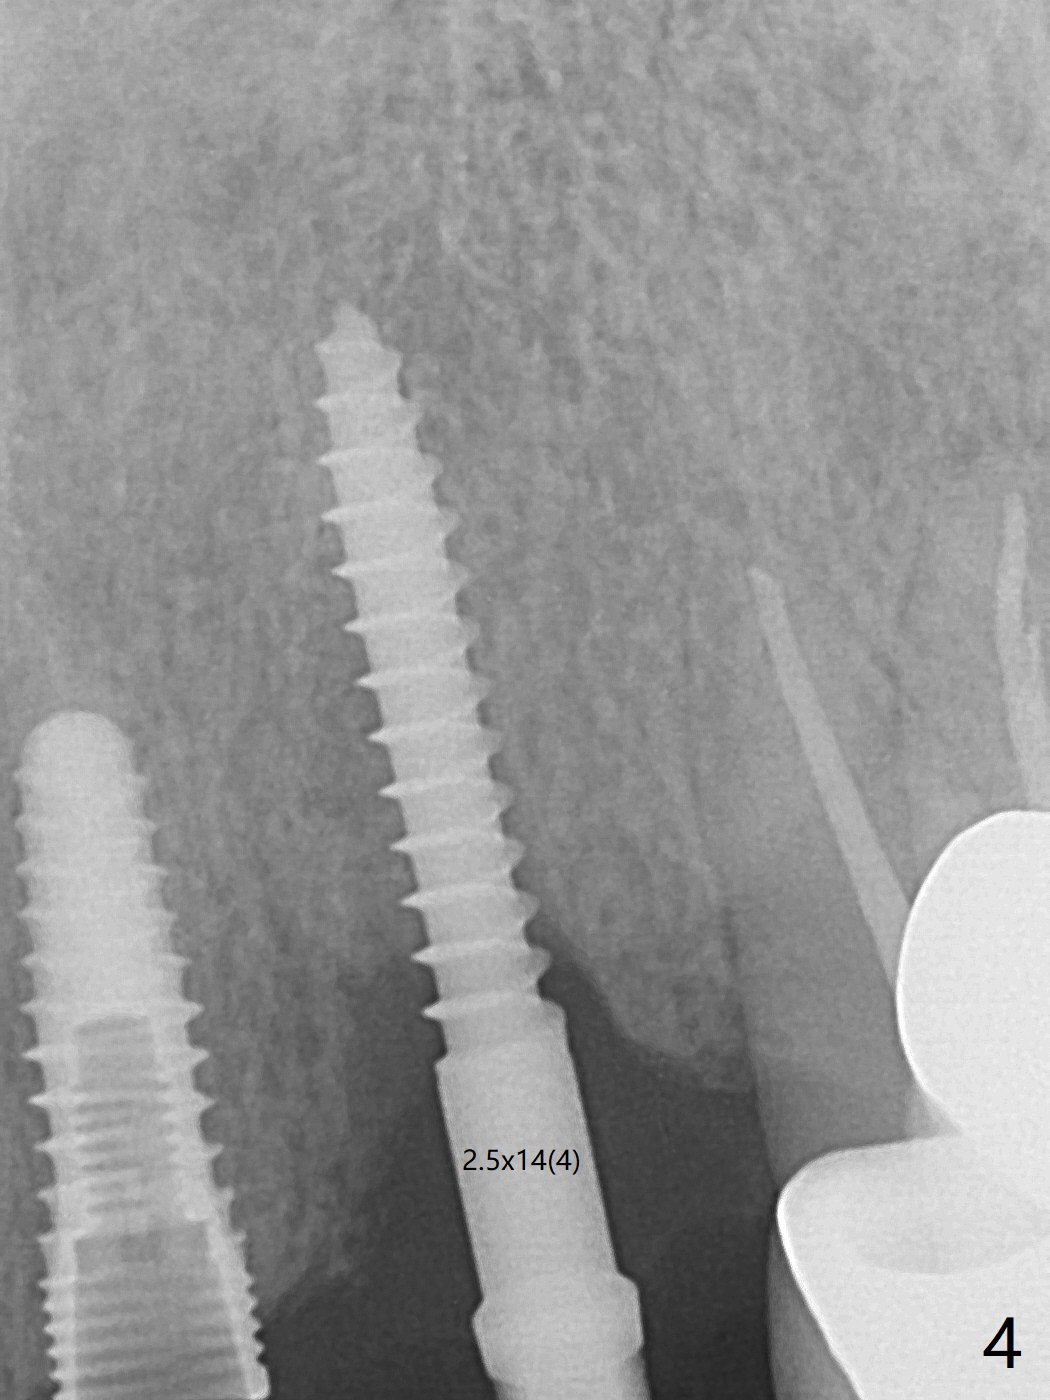

M

Incision shows exposure of microthreads at #9 and major threads at #10 due to buccal placement (Fig.1). There is bone palatal to the implant at #10 (Fig.2 P), to which a new implant will move. After implant removal, a narrower 1-piece implant (2.5x14(4) mm) is placed palatally at #10 (Fig.3,4) in combination of guide and free hand. At the site of #9 after implant removal, the guide is not used; a 3x17 mm angled 1-piece implant is placed with bad trajectory (Fig.5,6). After re-adjustment (Fig.7), the implant is placed at the right orientation (Fig.8). It appears that the guide is helpful. Allograft is placed mainly buccally (Fig.9,10 *), followed by a piece of collagen membrane (Fig.11). After tension release, flaps are approximated (Fig.12). The buccal gingiva at #9 and 10 recede nearly 2 months postop (Fig.13). Less recession at #9 is associated with more inflammation (Fig.14). The margin of the provisional is adjusted for gingival margin down growth and easy self cleaning with Water Pik (Fig.15). One month later, the gingival inflammation reduces, while there is no obvious buccal collapse (Fig.16,17). Impression is taken after laser gingivectomy nearly 4 months postop (Fig.18). While the gingiva around the implant at #9 is inflamed (periimplantitis?), the gingival cuff at #10 is well formed 5.5 months postop immediately before cementation (Fig.19). The buccal concavity at #10 is minimal (Fig.20). The gingival inflammation at #9 will be hopefully resolved after cementation of the final restorations (Fig.21). There appears to be new bone formation around the coronal implant threads 5.5 months postop (immediately post cementation, Fig.22). The microthreads at #9 may be not covered by the bone, the reason for the gingival erythema. The redness at #10 is asymptomatic 5.5 months post cementation (Fig.23). 粘固后两年牙槽嵴骨质并没有再生(图二十四),说明第一术中植体必须植入骨下(基台部分要长,否则难于修复),第二牙槽嵴处不应该有压力,植入2.5毫米植体,最后钻头应该是2.5毫米,骨下1-3毫米(尝试项目)。